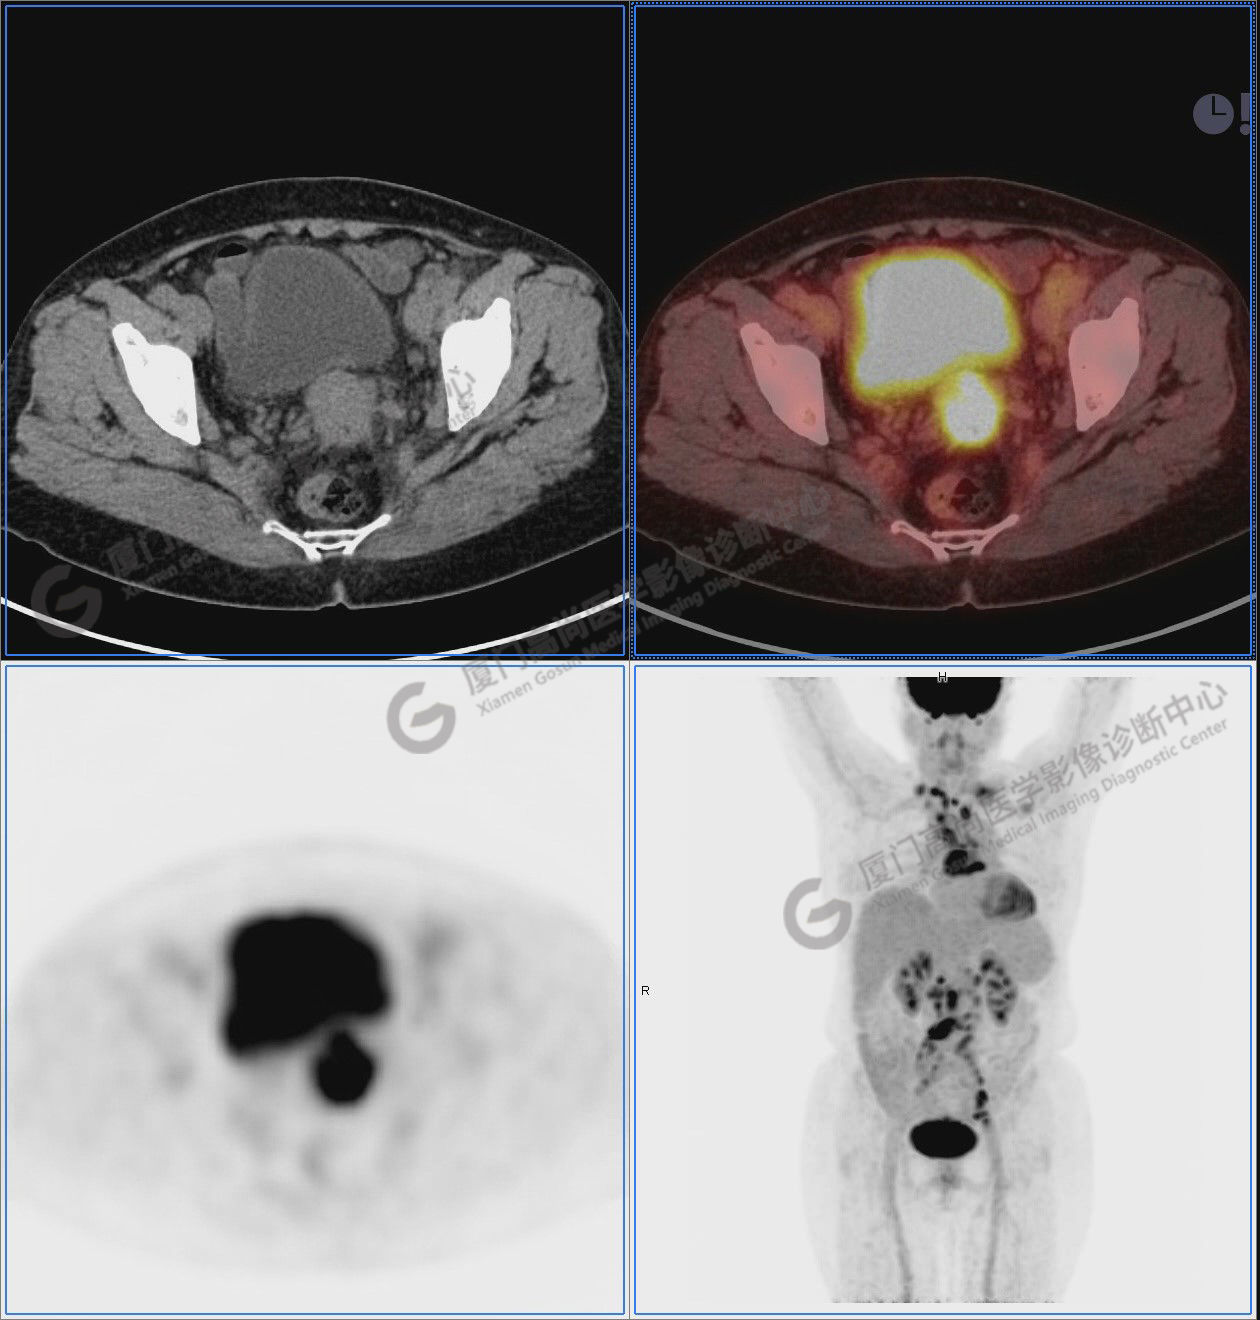

圖12-13:延遲2小時后,宮頸腫塊糖代謝進一步增高。

圖12

圖13